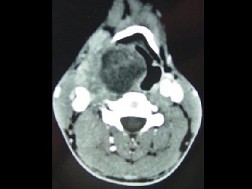

男,41岁,右侧咽部不适两年余,有异物感,声音嘶哑,CT如图所示,最可能诊断为 ( ) EBH-00941.jpg EBH-00942.jpg EBH-00943.jpg EBH-00944.jpg

题型: 单选题 分类: 耳鼻喉(头颈外科)学

• A.咽旁转移癌

• B.咽旁神经鞘膜瘤

• C.颈动脉体瘤

• D.咽旁淋巴瘤

• E.小唾液腺瘤